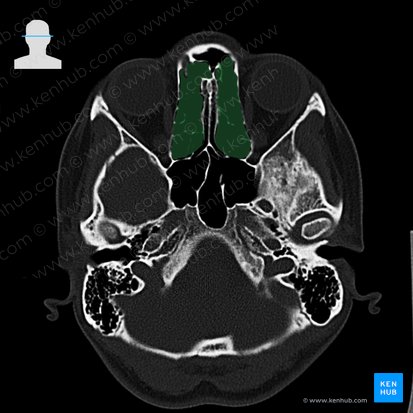

Paranasal sinuses

Ethmoidal cells (sinuses)

The ethmoidal sinuses, or commonly known as ethmoidal cells, are small spaces located in the ethmoid bone. More specifically, they are located between the nasal cavity and the orbit.

These cells can be divided into three groups that include:

• The anterior ethmoidal cells are drained to the middle nasal meatus via the ethmoidal infundibulum.

• The middle ethmoidal cells are drained into the middle nasal meatus. The middle cells are also known as “bullar cells” from a bulge they form on the middle nasal meatus (ethmoidal bulla).

• The posterior ethmoidal cells are drained into the superior nasal meatus.

The ethmoidal cells are innervated by the anterior and posterior ethmoidal branches of the nasociliary nerve, the branches of the ophthalmic nerve (CN V1).  The blood supply is provided via the anterior and posterior ethmoidal arteries.